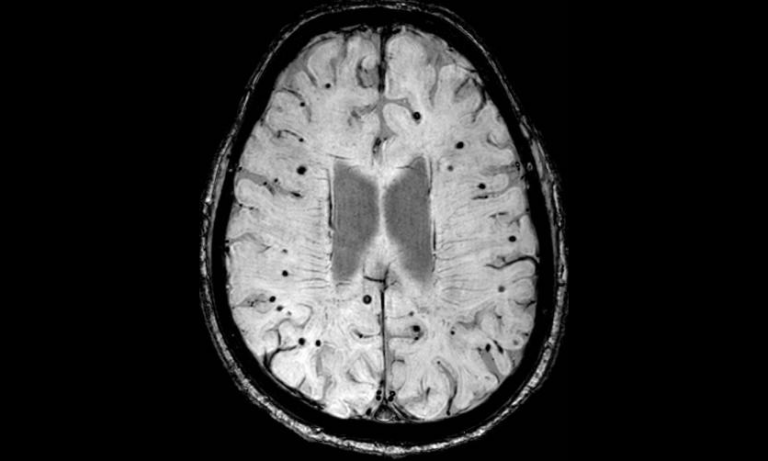

Susceptibility Weighted Imaging (SWI)

Stroke is often associated primarily with a blockage of a blood vessel causing an interruption to blood flow to the brain. However, haemorrhagic strokes (bleeding within the brain tissue) are another common. SWI is particularly sensitive to blood products due to the magnetic properties of iron rich blood. SWI enables the visualisation of even the smallest amounts of bleeding in the brain, enabling exact characterisation of the type and extent of stroke, guiding treatment decisions, and predicting patient outcomes.